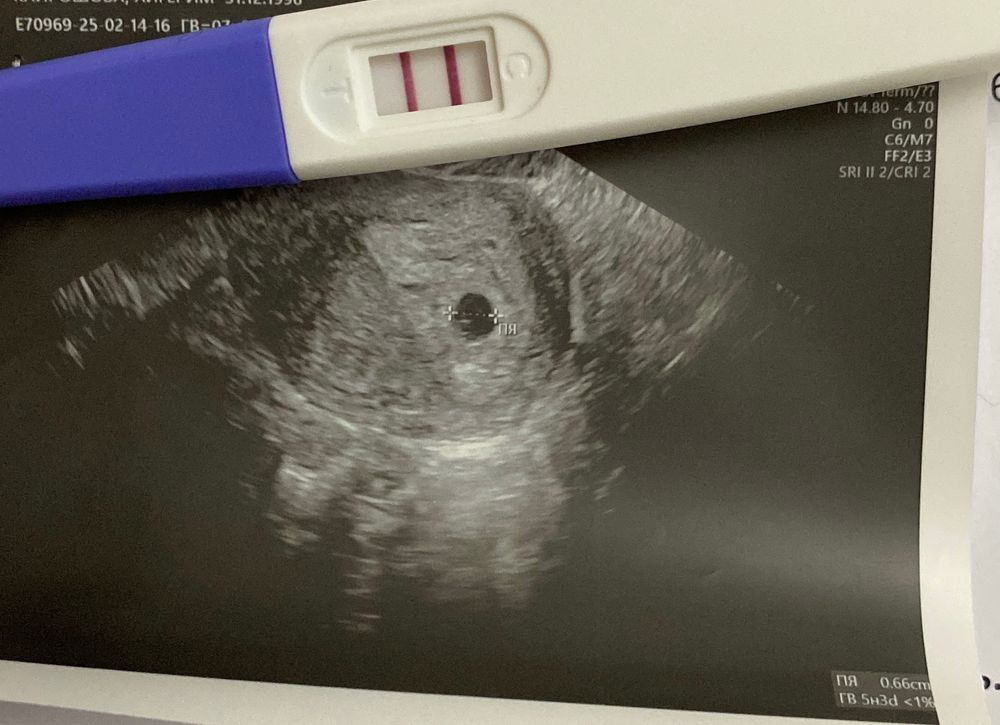

Узи в 22 дпо❤️

Вчера увиделась с малышом❤️

пя 6,6мм, жм 2,5мм соответствует сроку. за эмбриончиком и сердцебиением, даст бог, пойдем через две недели🥰